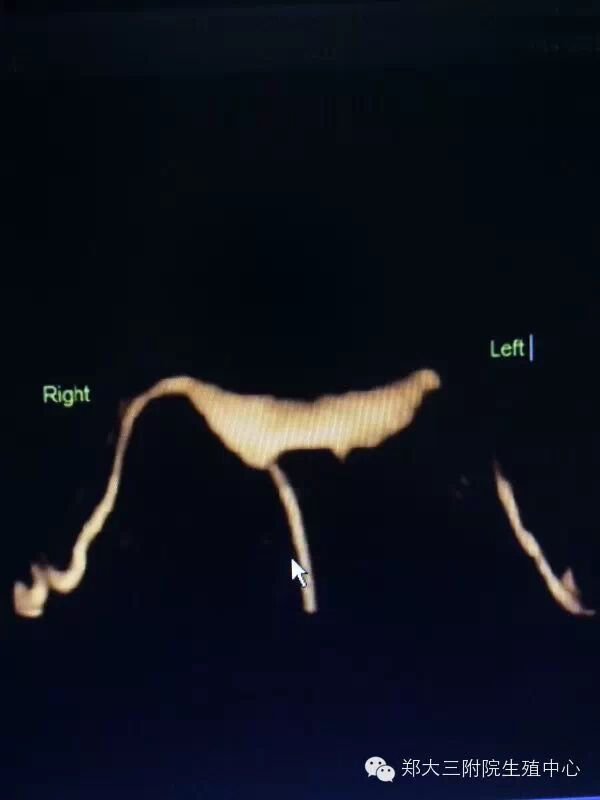

子宫输卵管超声造影(3D/4D-Hycosy)是在三维/四维阴彩下将造影剂经置入宫腔的导管注入子宫和输卵管,显示子宫腔和输卵管形态、位置、以发现宫腔和输卵管内病变、畸形以及评估输卵管通畅性的一种检查方法。

2、图像清晰、可三维立体成像、四维动态录像显示子宫、输卵管、盆腔造影的过程,更直观,便于临床医师观察;

3、对子宫输卵管畸形可明确诊断;

4、对输卵管异常显影如僵硬、扭曲、纤细、角状反折或盘曲的判断更精确;